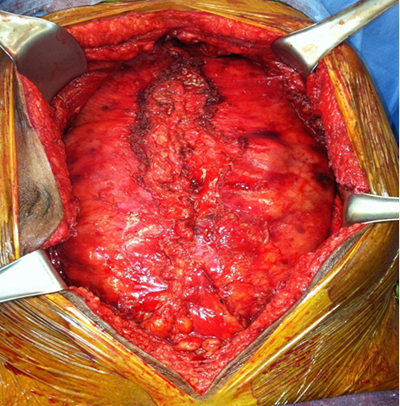

顱內血腫圖片

硬膜下血腫 (7)

硬膜下血腫 (8)

硬膜下血腫 (9)